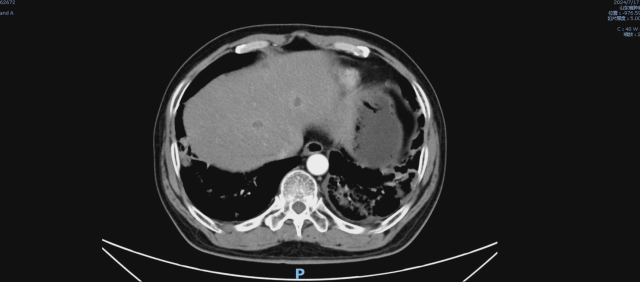

伏罗尼布治疗后,2024-09-09 复查CT

1. 考虑双肺炎症改变,较前范围减小,建议复查

2. 双肺多发结节,较前减小。

3. 双肺多发纤维灶。

4. 心包积液。

5. 肝内多发低密度病变,结合病史,不除外转移瘤可能,较前部分减小:建议必要时 CT 增强扫描进一步检查。

6. 考虑:肝左叶囊肿。